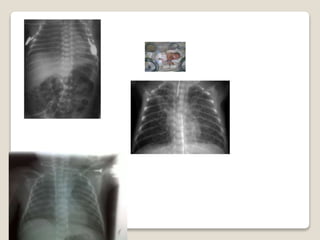

 PULMONARES

PATOLOGIA FRECUENTE DELRNPr.  PULMONARES  GASTROINTESTINAL  INMUNOLOGICO  SISTEMA NERVIOSO – OFTALMOLOGICOS  CARDIOVASCULAR  ENDOCRINO